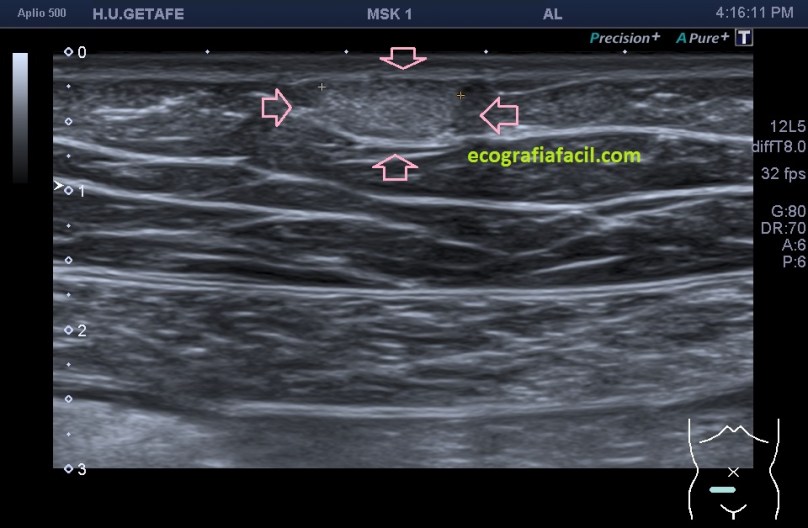

La estructura que estamos estudiando en este Caso 1, en las imágenes 1 a 6, es el estudio de protocolo de cualquier lesión, localización (flechas rosas), medición, vascularización. La 7 te marca una situación habitual en el estudio de los lipomas, y es que la paciente se nota un bulto, pero en la misma exploración descubrimos más, como es la pequeña lesión hiperecogénica que está justo al lado de la lesión mayor y palpable. Algunos de ellos, repito, pueden ser imperceptibles para la paciente, como era este caso. La imagen 8 es otra lesión próxima que sí era palpable.

En este caso las lesiones son todas hiperecogénicas comparativamente con el tejido hipoecogénico de la grasa del tejido celular subcutáneo. Son más o menos ovaladas, su eje largo es paralelo a la piel, no tienen vascularización y tienen medidas distintas. El diagnóstico final fue de lipomas. La paciente tenía más en la extremidades.

Cuidado, estas lesiones pueden presentarse hipoecogénicas, en ocasiones es complicado encontrarlos y es el reborde el que nos marca la posición de la lesión.

Por otro lado es muy importante la vascularización y el crecimiento de la lesión, ya que estos tumores benignos ni tienen vascularización y su crecimiento es lento.